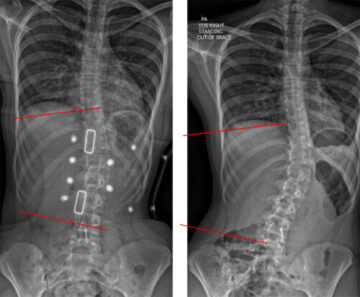

درجات الجنف بالصور: دليل شامل للأهل لفهم شدة اعوجاج العمود الفقري وخيارات العلاج يُعد فهم درجات اعوجاج العمود الفقري (الجنف) خطوة أساسية لكل أسرة لديها طفل مصاب بهذه الحالة. فعند سماع أرقام مثل 20

ما معنى ارتفاع زاوية كوب في اعوجاج العمود الفقري وكيف يؤثر على طفلك؟…

ما معنى ارتفاع زاوية كوب في اعوجاج العمود الفقري وكيف يؤثر على طفلك؟ يشير مصطلح زاوية كوب (Cobb Angle) إلى المقياس الطبي الأساسي المستخدم لتحديد شدة اعوجاج العمود الفقري (الجنف). وعندما تكون زاوية كوب

ما هي زاوية كوب التي يُشخَّص عندها اعوجاج العمود الفقري؟…

ما هي زاوية كوب التي يُشخَّص عندها اعوجاج العمود الفقري؟ عند تشخيص اعوجاج العمود الفقري، غالبًا ما يسمع الأهل والمرضى مصطلحًا طبيًا يتكرر كثيرًا وهو زاوية كوب. في هذه المرحلة، يبدأ القلق وتكثر الأسئلة،